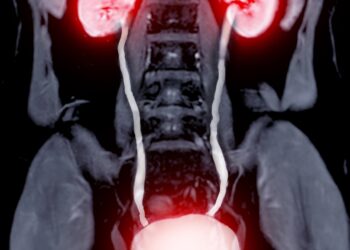

Skaityti daugiauDetailsInkstų augliai – tai pakitusių ląstelių dariniai, susidarę viename arba abiejuose inkstuose. Šie dariniai gali būti gerybiniai, tuomet nekelia pavojaus...

Skaityti daugiauDetailsInkstų akmenys – tai dažna šlapimo takų būklė, kuri pasireiškia, kai inkstuose susiformuoja kietos masės ar kristalai iš įvairių medžiagų,...

Skaityti daugiauDetailsInkstų vėžys vystosi, kai inksto audinyje pradeda nekontroliuojamai daugintis pakitusios ląstelės. Kol kas mokslininkai tiksliai nežino, kas nulemia šias ląstelių...